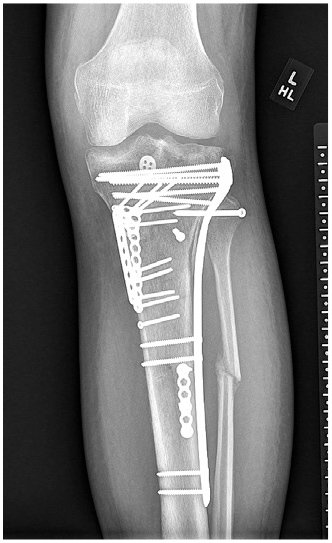

Radiographs at 6 weeks postoperatively showed the fracture was healing (Fig. 5), and the patient had regained flexion to just beyond 90°. By 3 months, he had regained nearly normal range of motion (Fig. 6), had a stable knee exam, and normal gait.

Figure 5: AP radiograph at 6 weeks postoperatively shows maintenance of alignment.